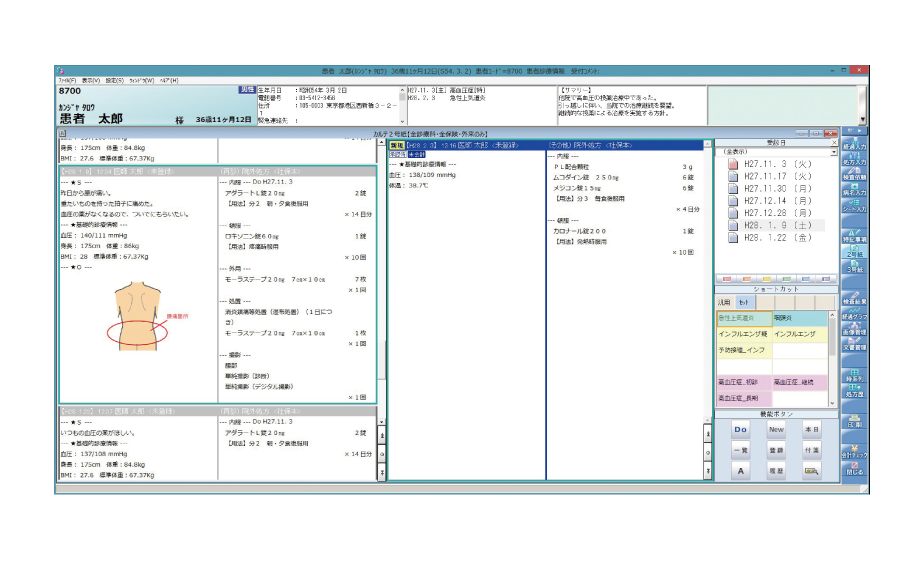

見やすい画面で直感的に操作、電子カルテをスマートに使いこなせます。

ワンタッチセット入力

ワンタッチボタンを指でタップするだけで、よく使う所見や処方などをかんたんに入力できます。

ワンタッチボタンは自由に設定できるので、診療内容を入力する際に必要なものを任意に登録できます。入力は指だけではなく、ペンタッチでもマウスクリックでも可能です。

多彩な機能が記録を残す・患者さんに説明するシーンをスマートにサポートします。

入院専用画面で、入院患者の情報を一元管理します。

入院受付や入院会計にも対応し、入院事務もスピーディーに処理します。